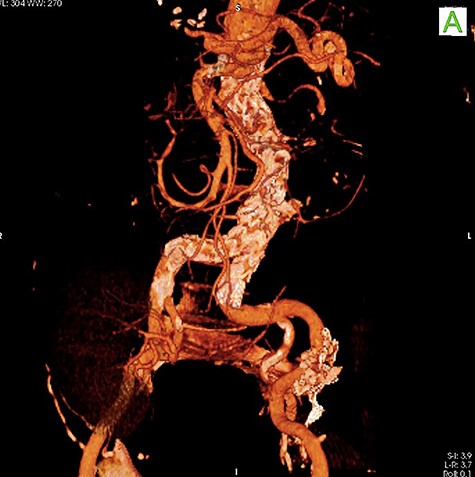

A 59-year-old male presented with end-stage liver disease secondary to hepatitis C and end-stage renal disease. On CT scan, an abdominal aortic aneurysm was incidentally found with a diameter of 4*3.8 cm (Fig. 1).